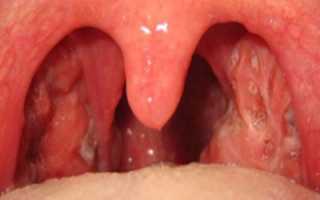

Ангина – это инфекционное заболевание, которое локализуется в миндалинах.

Ангина зачастую связана с попаданием патогенных бактерий на слизистую при ослабленном иммунитете.

Иногда заболевание может быть осложнением после простуды, вирусного заболевания.